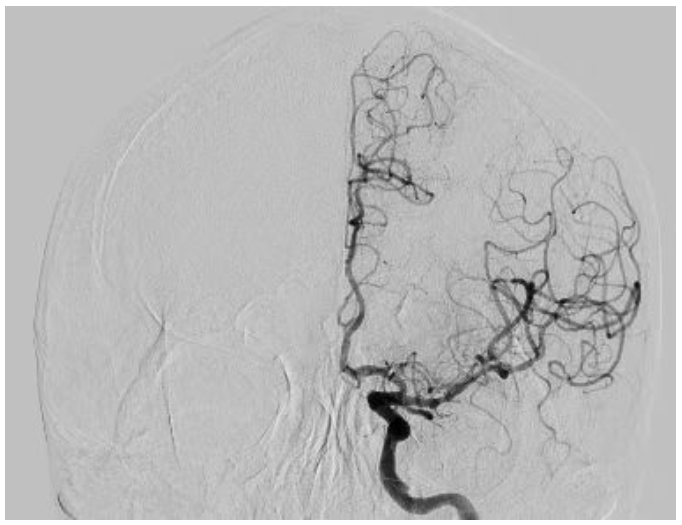

术中从桡动脉建立一条通路,先后完成了冠状动脉及椎动脉、颈动脉、脑动静脉造影,术中发现患者冠状动脉回旋支重度狭窄,前降支中度狭窄,双侧颈内动脉、左侧大脑中动脉轻-中的狭窄。综合患者情况及造影结果,冠状动脉有介入指征,脑血管无需介入处理,最终决定对患者冠状动脉重度狭窄行介入治疗,术中结合 IVUS(血管内超声),成功「重塑」患者冠状动脉,恢复心脏供血。(术者:杨征 助手:何涛志)